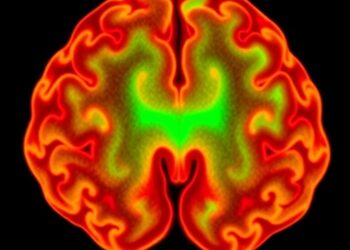

HDAC1 Condensation Links to Temozolomide Response in Glioblastoma

Recent advances in cancer research have uncovered a startling mechanism behind the resistance of glioblastoma multiforme (GBM) to the chemotherapeutic ...

Los Angeles, CA – In a groundbreaking advancement for brain cancer research, scientists at the Terasaki Institute for Biomedical Innovation ...